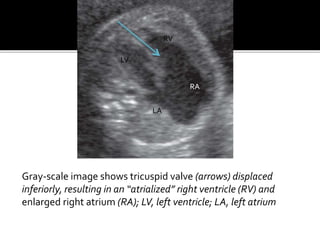

 INFERIOR DISPLACEMENT OFTHE

TRICUSPIDVALVE( +TETHERED

ATTACHMENT OFTHE LEAFLETS

+TRICUSPID DYSPLASIA +RIGHT

VENTRICULAR DYSPLASIA ) .

 7% of cardiac anomalies , may be associated

with structural cardiac defects as pulmonary

atresia or stenosis, arrhythmias and

chromosomal anomalies .

 Readily detected in utero.

 Sonographic diagnosis rests on recognition of

apical displacement of the tricuspid valve into

the right ventricle- the most reliable sign ,an

enlaged RA containing a portion of the atrialised

RV ,and a reduction in the size of functional RV

.d/d- tricuspid valvular dysplasia.

Gray-scale image shows tricuspid valve (arrows) displaced

inferiorly, resulting in an “atrialized” right ventricle (RV) and

enlarged right atrium (RA); LV, left ventricle; LA, left atrium